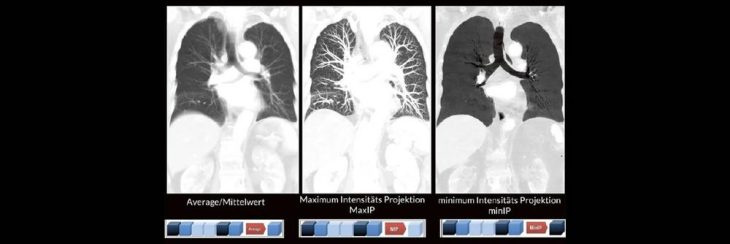

Professor Dr. med. Marc Brockmann WEITERENTWICKLUNGEN VON KOPF BIS FUSS BEIM VC Oberstarzt Dr. med. Stephan Waldeck DEEP-LEARNING-REKONSTRUKTION IN DER NEURORADIOLOGIE Die CT ist ein essentielles Routine-Verfahren in der Neuroradiologie. Bei steigender Bildqualität konnte die Röntgendosis mit neuen Technologien in der letzten Dekade deutlich gesenkt werden, was für die zielgerichtete und möglichst schonende Behandlung vonRead more about DEEP-Learning-Rekonstruktion in der Neuroradiologie (Webinar | Online)[…]